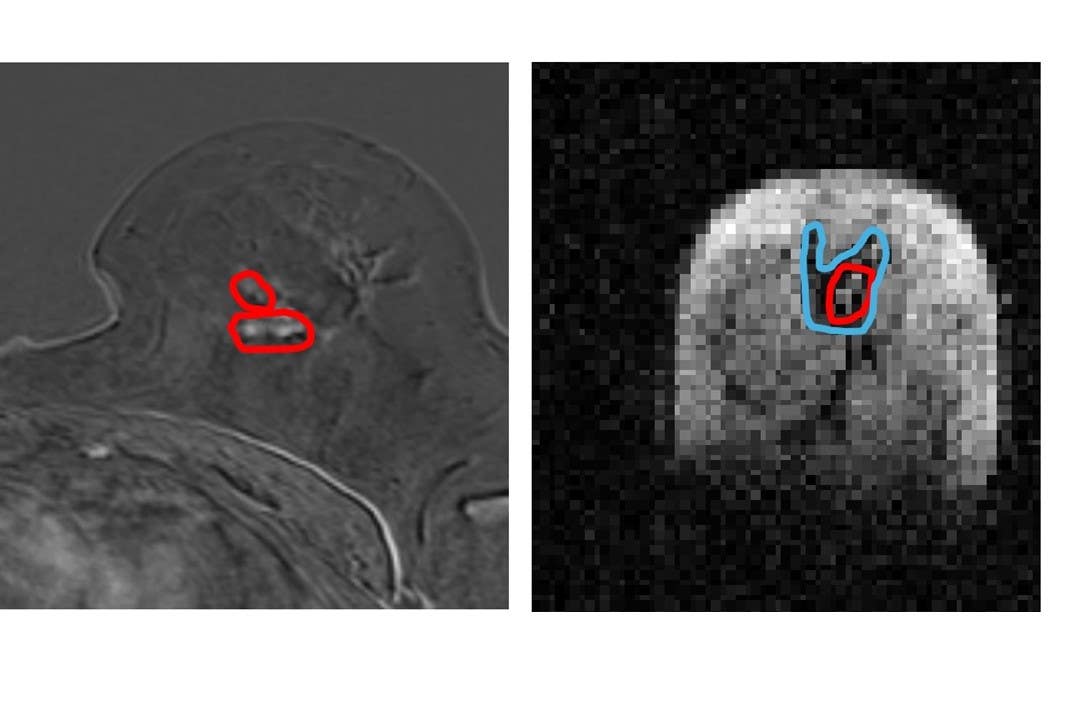

They found that the FCI scanner could distinguish tumour material from healthy tissue with more accuracy than current MRI methods.

The university described the scanner as “groundbreaking” and said it could identify “previously undetectable cancer tumour invasion”.

Researchers said the new technique could potentially more accurately outline these tumours and reduce the need for such repeat operations.